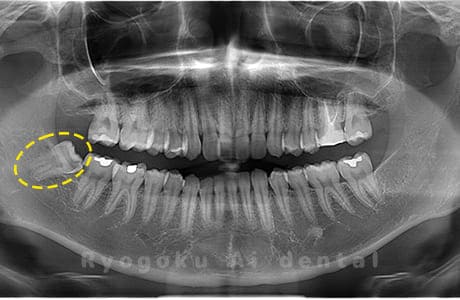

Case01

- 原因

- 水平埋伏智歯

- 治療内容

- 下顎の水平埋伏智歯を抜歯

<リスク・副作用>

手術後は痛み、腫れ、痺れなどの副作用が生じる場合があります。